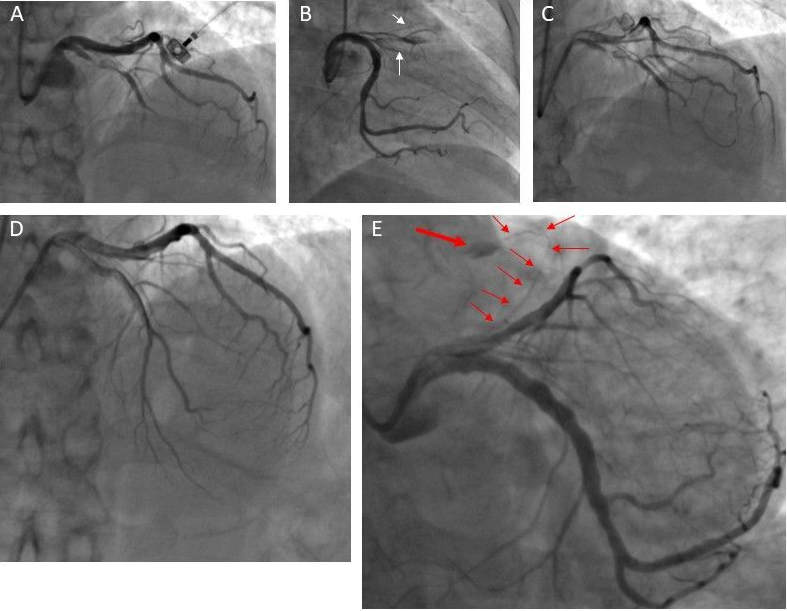

An emergency transradial coronary angiography in a 68-year-old woman demonstrated sub-total occlusion of the proximal left anterior descending artery (LAD) (Figure 1A). Wiring was challenging because of a funny arteriole network arising from the proximal LAD (Figure 1B; Video 1), wherein the guidewire was entering inadvertently (Video 2). The lesion was finally crossed with a workhorse wire (Figure 1C). After pre-dilatation and implantation of a 2.5 x 30-mm zotarolimus-eluting stent, intracoronary tirofiban was administered due to slow flow. The final angiographic result was satisfactory (thrombolysis in myocardial infarction [TIMI] 3 flow) (Figure 1D). However, in the last cine-angiographic shots, a minor leak was noticed distally from one of the arterioles arising from the proximal LAD (Figure 1E; Video 3). A beside echocardiogram excluded pericardial effusion.